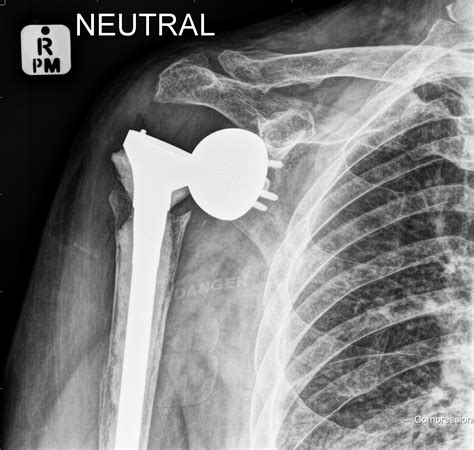

• X-rays: Imaging tests can confirm the dislocation and rule out fractures or other injuries.

• inferior shoulder dislocation xray

• inferior shoulder dislocation xr